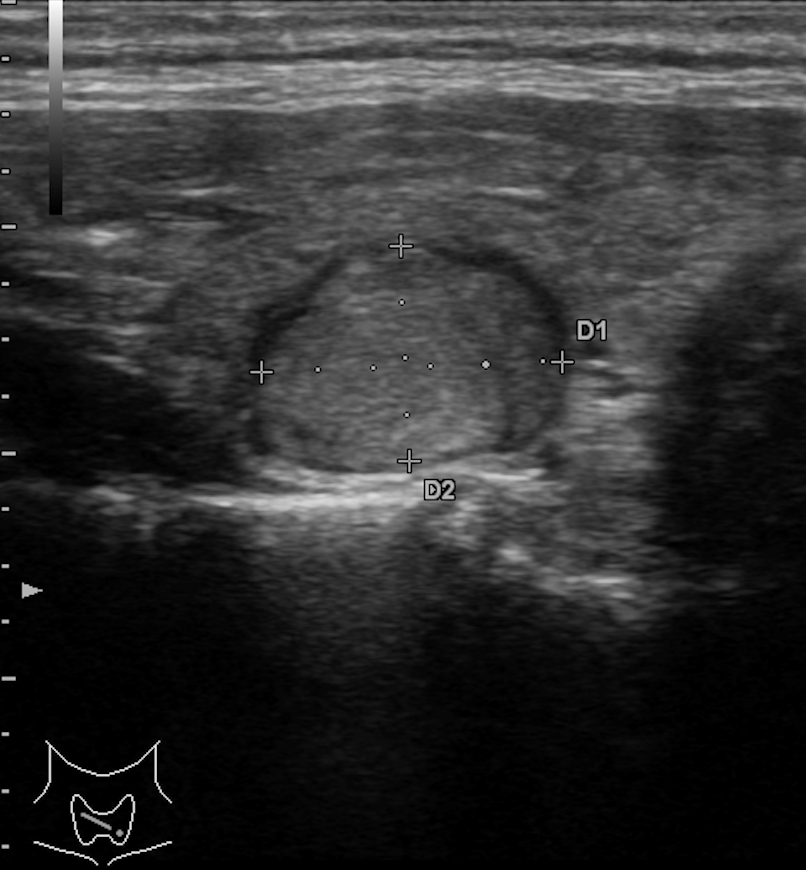

TI-RADS 4. Узлы более 1,0 см в диаметре с “малыми” признаками злокачественности для выполнения ПУНКЦИИ (рис. 3):

- солидные узлы, равномерно или неравномерно умеренно пониженной эхогенности;

- солидные узлы изо- или гиперэхогенные, имеющие “малые” признаки злокачественности:

– гипоэхогенные включения;

– округлая/шаровидная форма;

– неравномерно утолщенное хало;

– макрокальцинаты.

Рис. 3. TI-RADS 4: а – узел шаровидной формы, с ровными и четкими контурами, умеренно пониженной эхогенности, с участками более низкого эхо, с макрокальцинатом. Узел окружен тонким хало (фолликулярная неоплазия); б, в, г (поперечное и продольное сканирование левой доли ЩЖ) – изоэхогенные узлы с гипоэхогенными включениями, с четкими контурами, с тонким хало (фолликулярная аденома); д – изоэхогенный узел с гипоэхогенными включениями, с неравномерно утолщенным хало (фолликулярный рак).